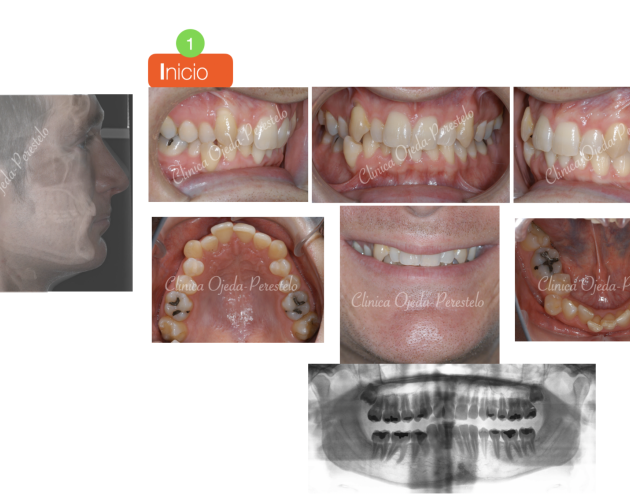

Mordida Abierta de molar a molar Casos de Éxito - Adultos

Clase II esquelética con Cirugía de Avance Md Casos de Éxito - Ortodoncia Plástica (Invisalign/Angel) - Adultos

Asimetría Facial en Clase III ósea y C.Ortognática Casos de Éxito - Mordida Cruzada - Adultos - Cirugía Ortognática

Clase III esquelética en dentición temporal Casos de Éxito - Niños

Clase II esquelética en niño con apnea moderada Casos de Éxito - Niños

Caso Ortodoncia Lingual Superior con Vestibular Inferior Casos de Éxito - Ortodoncia Lingual

Caso Multidisciplinar: Ortodoncia- Coronas sobre Implantes Casos de Éxito - Adultos - Casos Multidisciplinares

Caso Multidisciplinar: Ortodoncia-Implantes-Pónticos-Bioestética Casos de Éxito - Adultos - Casos Multidisciplinares

2ºMolar Mandibular Retenido Casos de Éxito - Dientes Retenidos

Caso Multidisciplinar: Ortodoncia-Implantes-Bioestética 11-21 Casos de Éxito - Casos Multidisciplinares

Caninos Maxilares Retenidos (13-23) + Bioestética 21-22 Casos de Éxito - Niños - Dientes Retenidos - Casos Multidisciplinares

Premolar Mandibular Retenido (35) Casos de Éxito - Niños - Dientes Retenidos

Clase II con Mordida Abierta Casos de Éxito - Ortodoncia Plástica (Invisalign/Angel) - Adultos

Clase II severa en Mandíbula Hipoplásica Casos de Éxito - Adultos - Cirugía Ortognática

Expansión Maxilar Asistida en Mord.Cruzada Casos de Éxito - Mordida Cruzada - Adultos - Cirugía Ortognática

Mordida Cruzada Unilateral con Apiñamiento Severo Casos de Éxito - Mordida Cruzada - Adultos

Mordida Cruzada Bilateral Casos de Éxito - Mordida Cruzada - Niños

Clase III esquelética en dentición definitiva Casos de Éxito - Niños

Mordida Cruzada con dolor Craneofacial Casos de Éxito - Ortodoncia Plástica (Invisalign/Angel) - Mordida Cruzada - Adultos

Clase III ósea severa con C.Ortognática Casos de Éxito - Mordida Cruzada - Adultos - Cirugía Ortognática

Asimetría Facial en Clase III ósea y C.Ortognática Casos de Éxito - Mordida Cruzada - Adultos - Cirugía Ortognática - Casos Multidisciplinares

Biprotusión esquelética con Sonrisa Gingival Casos de Éxito - Adultos - Cirugía Ortognática

Clase II osea de causa Md con Cara Larga Casos de Éxito - Adultos - Cirugía Ortognática

Clase II ósea con Resalte muy Aumentado y Extracciones dentarias Casos de Éxito - Adultos - Casos Multidisciplinares

Apiñamiento severo con molares con mal pronóstico Casos de Éxito - Adultos

Mordida Abierta Posterior con M. Cruzada en clase III ósea Casos de Éxito - Mordida Cruzada - Adultos

Clase III ósea tratada con Exo de cordales y Microtornillos Casos de Éxito - Mordida Cruzada - Adultos

Clase II con apiñamiento y sobremordida severa Casos de Éxito - Ortodoncia Plástica (Invisalign/Angel) - Adultos

Sonrisa gingival (encías) con Resalte Aumentado Casos de Éxito - Mordida Cruzada - Adultos

Clase III esquelética en dentición mixta Casos de Éxito - Niños

Canino Mandibular Retenido (33) Casos de Éxito - Dientes Retenidos

Mordida Cruzada y Abierta severa Casos de Éxito - Mordida Cruzada - Adultos

Ortodoncia-Implantes-Bioestética 22 Casos de Éxito - Ortodoncia Plástica (Invisalign/Angel) - Adultos - Casos Multidisciplinares

C Multidisciplinar: Orto Plástica + MASPE+ Corticotomías + Regen Casos de Éxito - Ortodoncia Plástica (Invisalign/Angel) - Mordida Cruzada - Adultos - Cirugía Ortognática - Casos Multidisciplinares

Mordida invertida en clase III (MARPE +Orto Plástica + elásticos Casos de Éxito - Ortodoncia Plástica (Invisalign/Angel) - Mordida Cruzada - Adultos